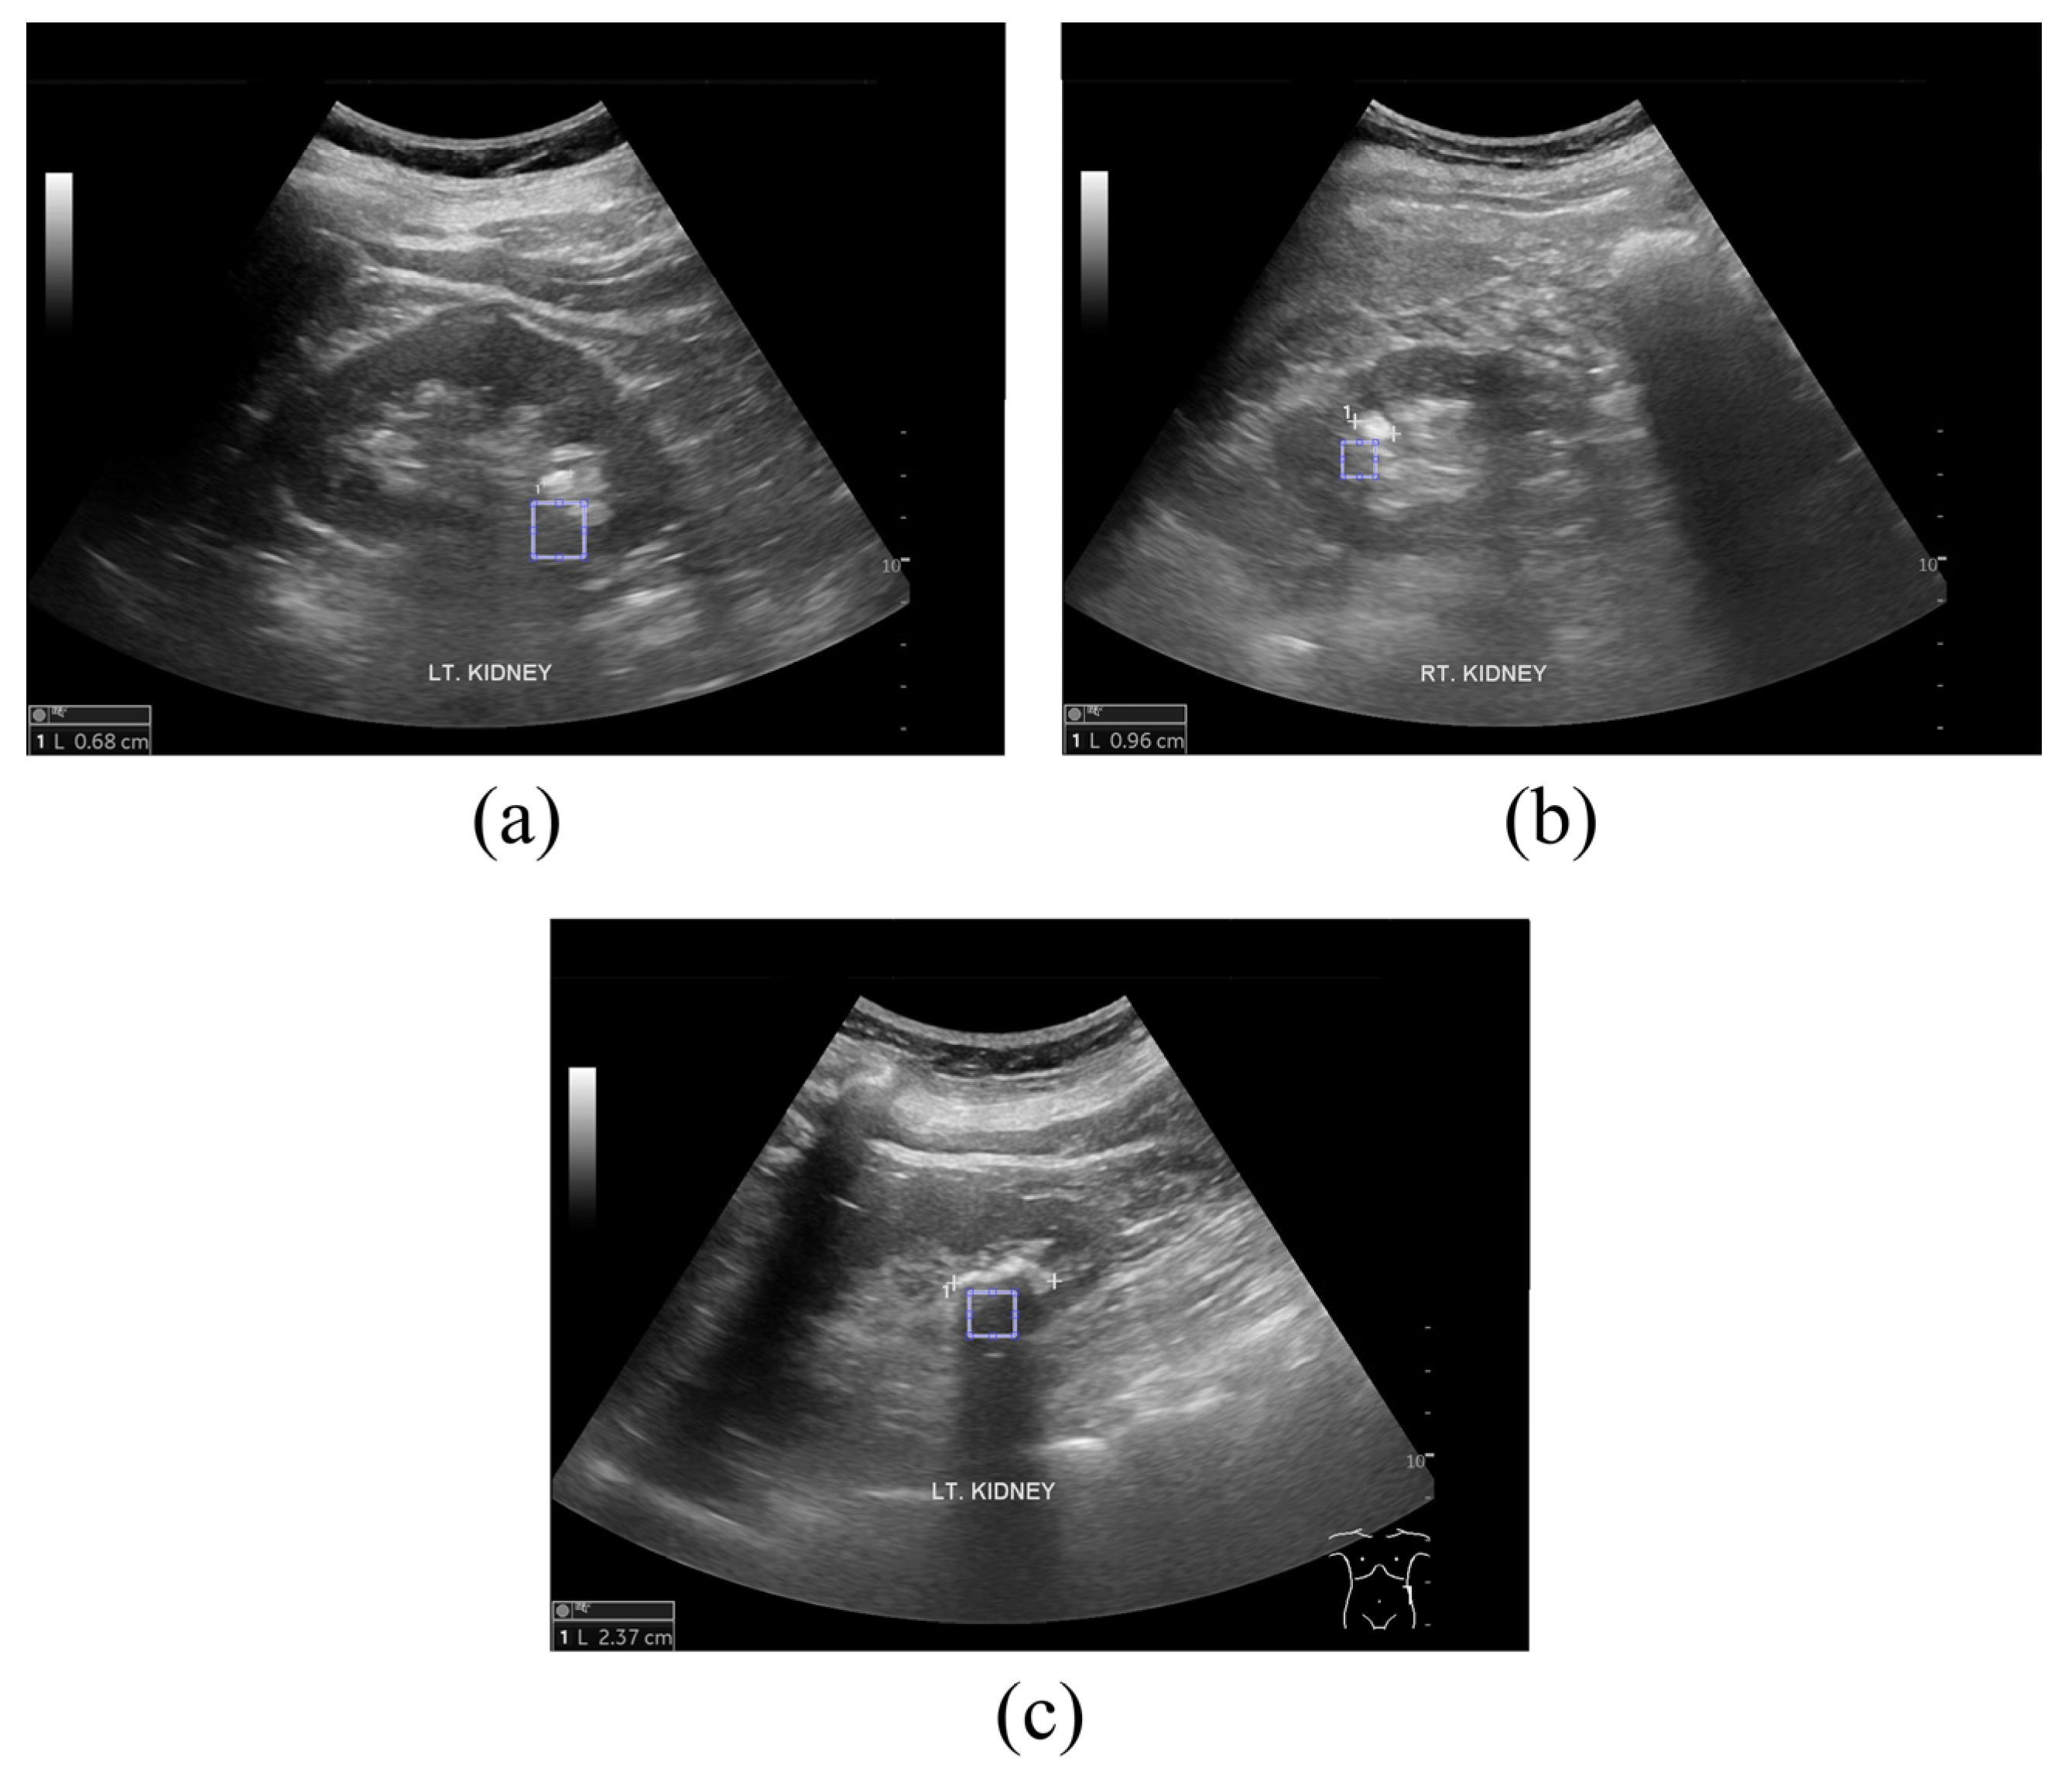

2.1. Ultrasound Image Acquisition

2.2. Proposed Framework to Determine Kidney and Gallbladder Stones Using the GLCM